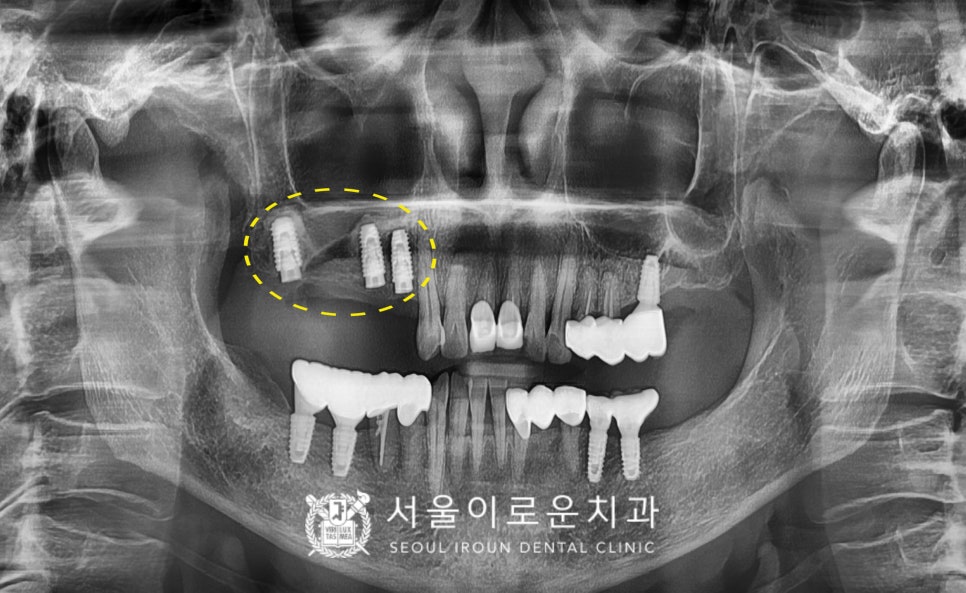

자연치아와 강도가 가장 유사하고

심미적인 지르코니아 크라운으로

보철을 마무리해드린 치료 후 모습입니다!

환.자분께서는

타원에서 아래턱 임플란트 진행 시

많이 아프고 불편하셔서

걱정을 많이 했었는데

통.증도 거의 없고

출혈도 잘 멎어서 만.족하셨으며

양측으로 편안한 식사가 가능하셔서

정말 좋아해하셨답니다.

(2023.09.11ㅡ>2024.03.26)